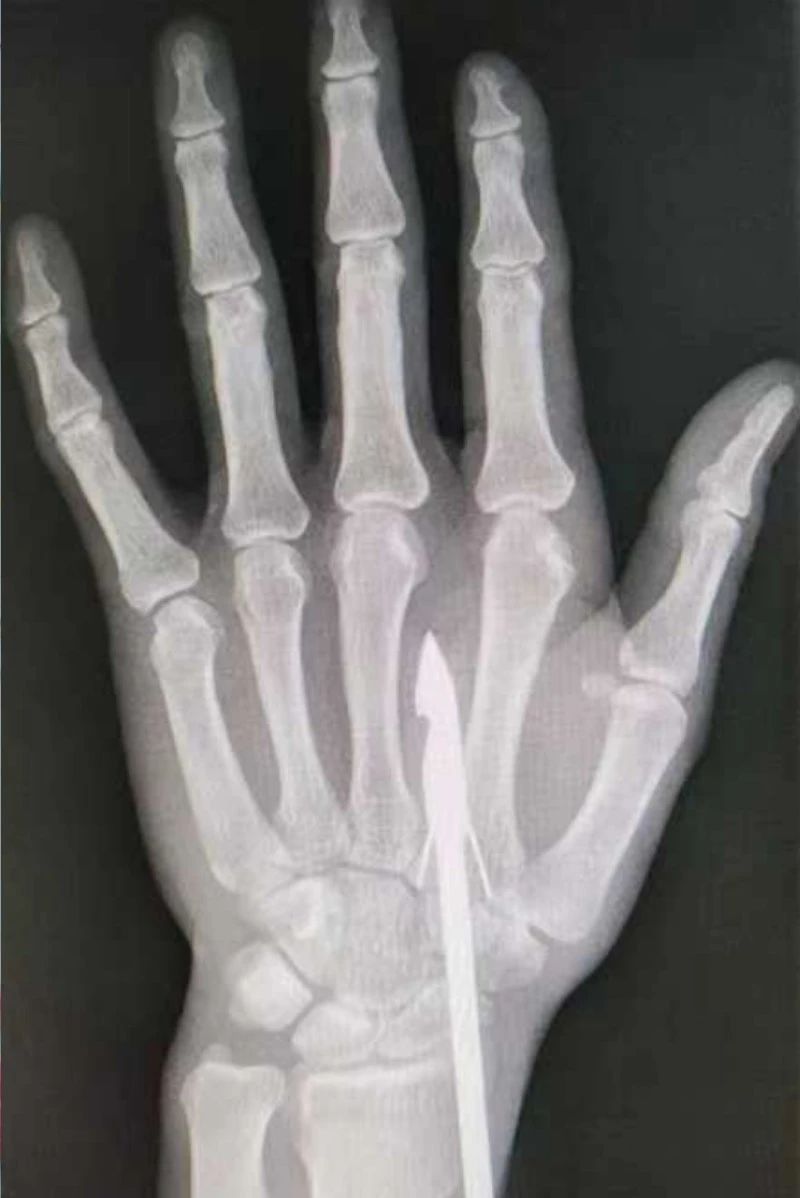

時間緊迫,每一秒的流逝都可能對傷者的手部功能造成不可逆的損害。接診醫(yī)生代彭威,迅速對傷者進行了初步檢查。他注意到,魚鉤已經(jīng)深深嵌入皮膚,情況遠比表面看起來復(fù)雜。沒有絲毫猶豫,立即安排了X線檢查以確認(rèn)魚鉤的位置及傷及范圍,以及急診化驗檢查以評估患者的整體狀況。

確保在取出魚鉤的同時,不對周圍的組織造成額外的傷害。8點15分左右患者在局部浸潤麻下進行手術(shù),經(jīng)探查后魚鉤未傷及重要血管、神經(jīng)及肌腱,經(jīng)過緊張的十分鐘,魚鉤終于被順利取出,隨后對傷口進行了仔細的清理和縫合,用敷料仔細包扎,確保傷口能夠順利愈合。